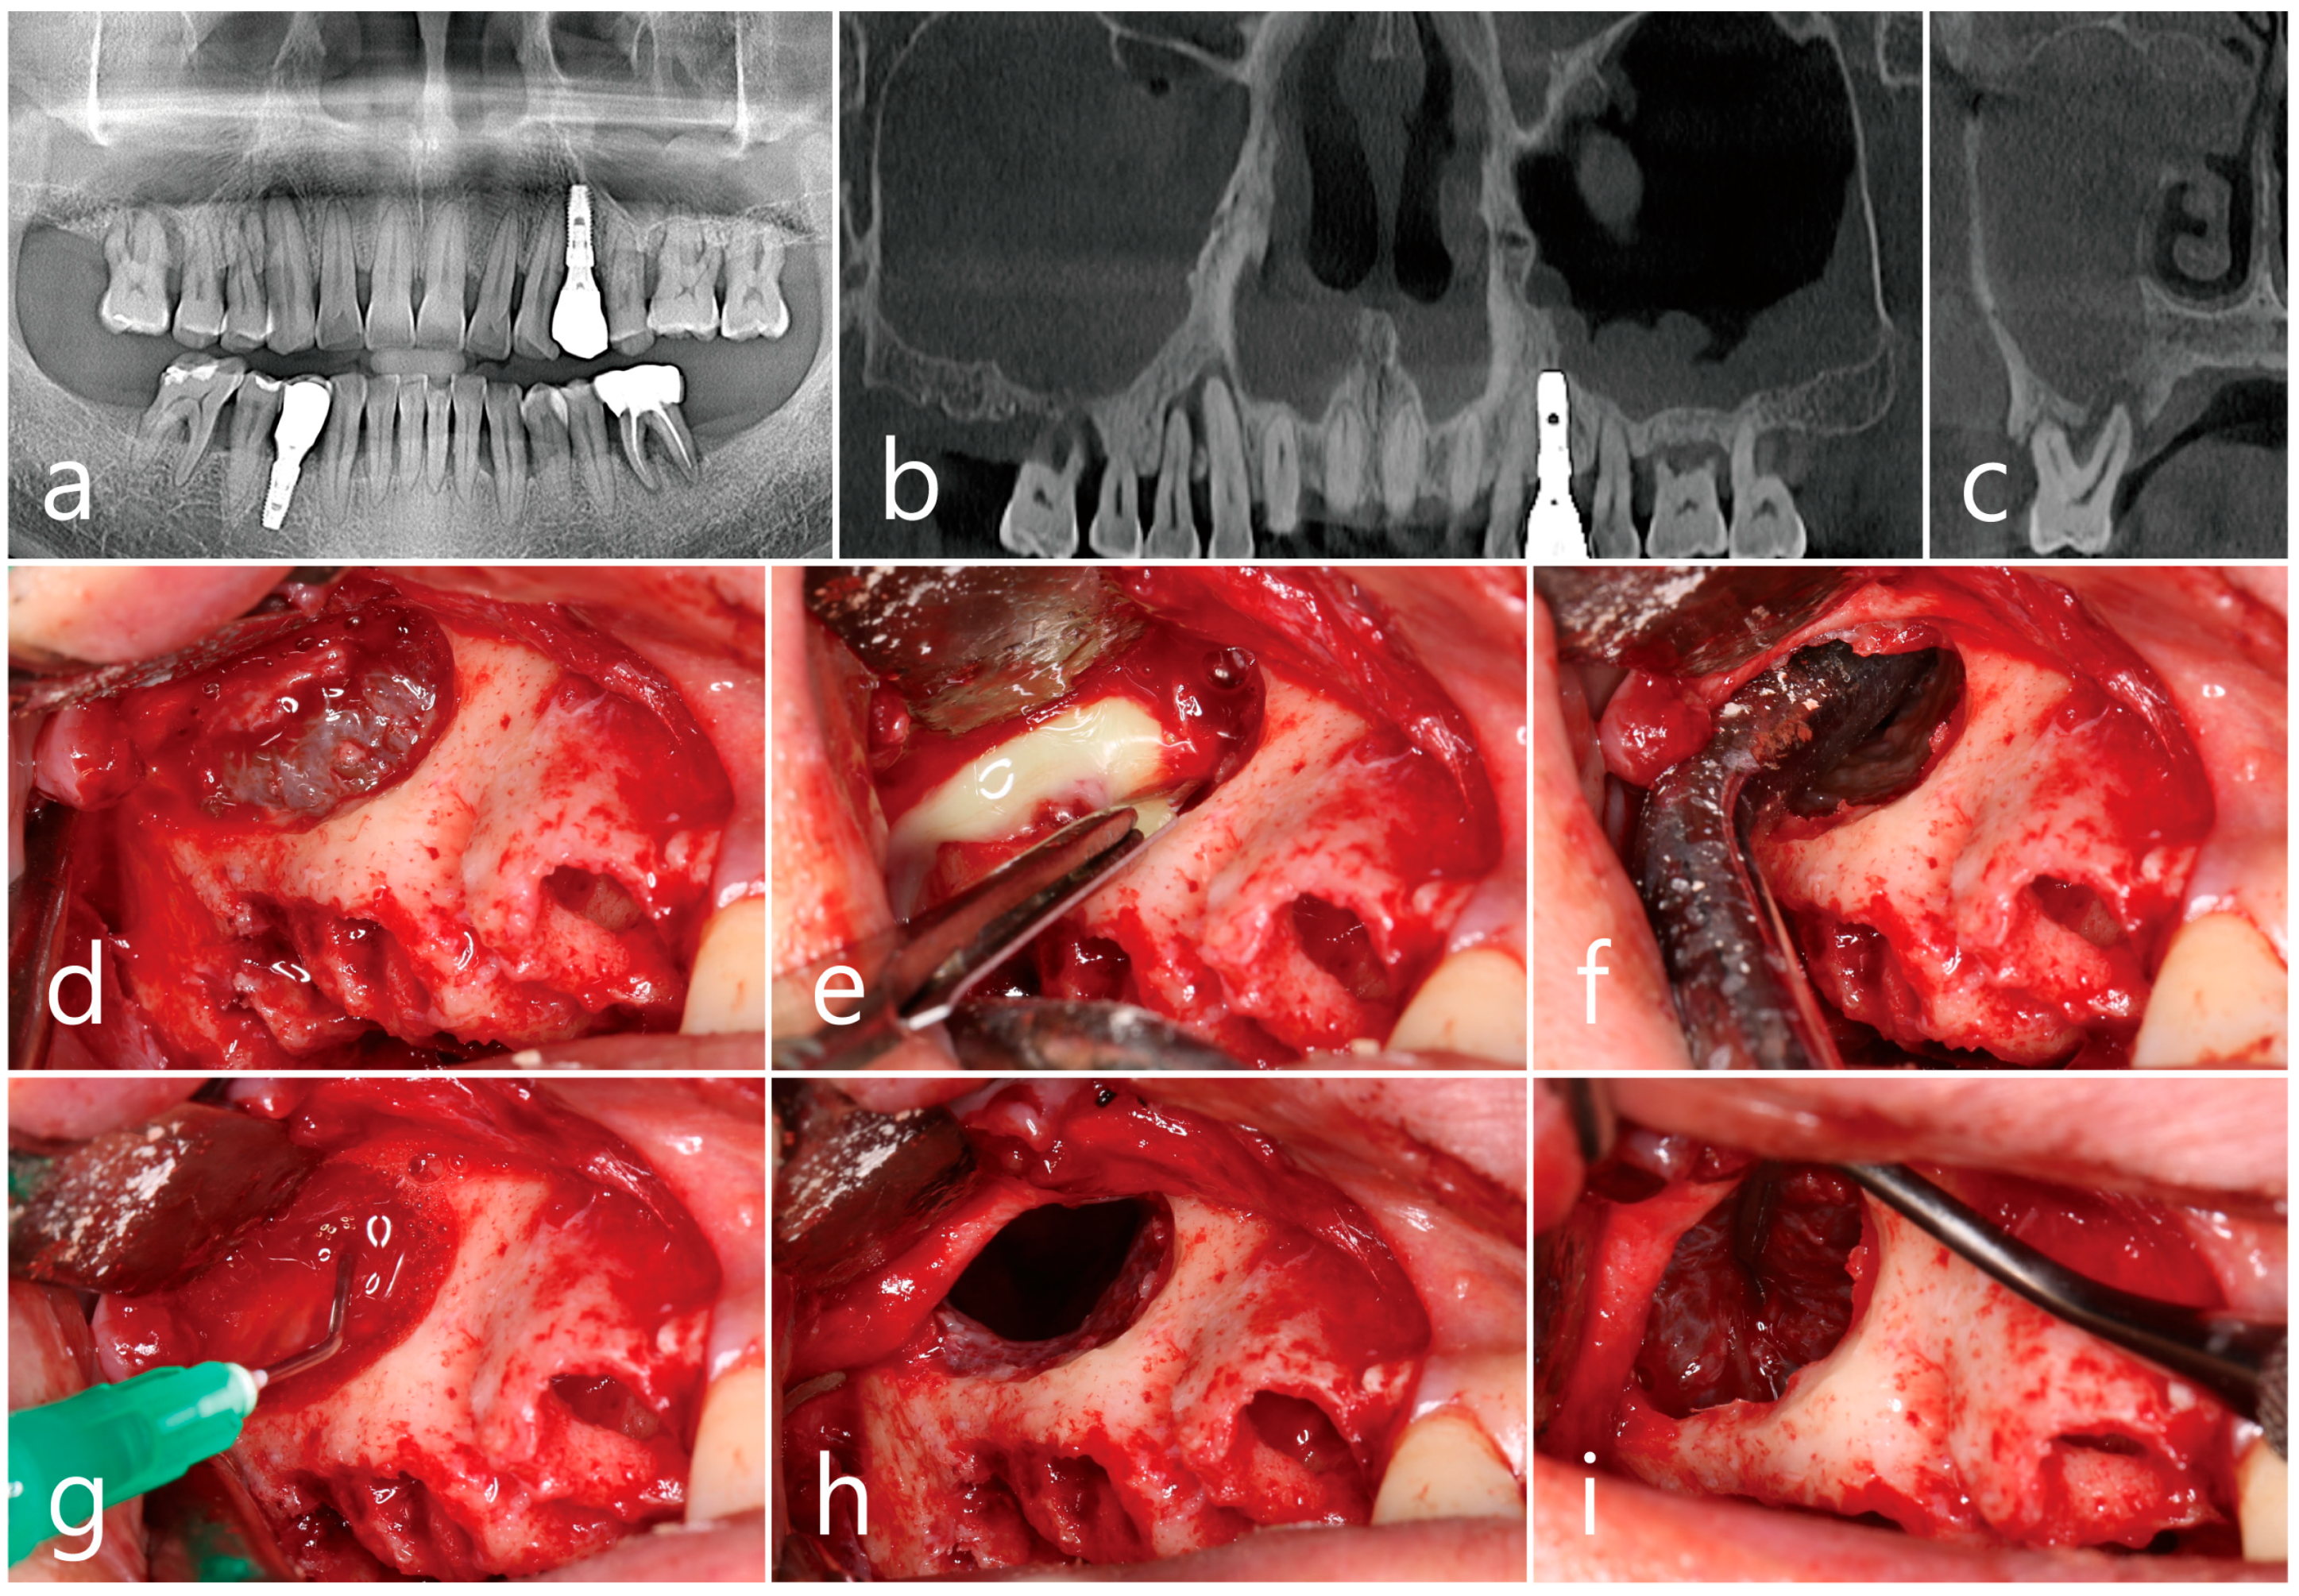

2.2. Case 2